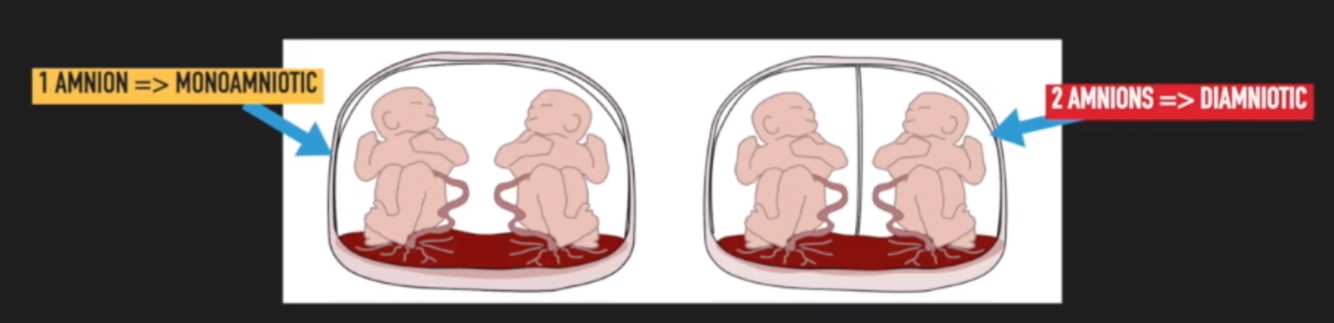

What is amnioncity?

Amnionicity = number of amnions (inner membranes) that surrounds foetus in a multiple pregnancy:

- Pregnancies with 1 amnion (all babies share amniotic sac) are monoamniotic

- Pregnancies with 2 amnions are diamniotic